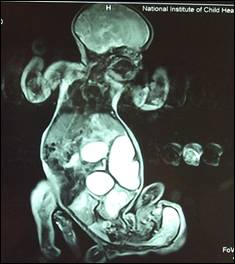

Figure 5: MRI of conjoined twins.